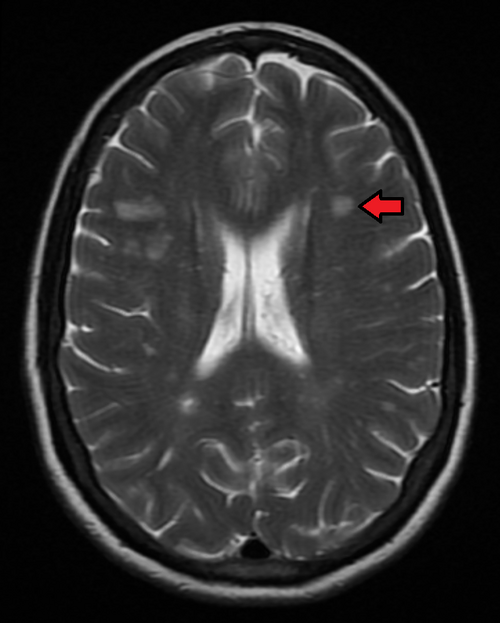

- Verfahren: kranielle und spinale MRT (primäre Bildgebung zur Diagnostik und Verlaufsbeobachtung bei MS)

“MSMRIMark.png” von James Heilman https://commons.wikimedia.org/wiki/File:MSMRIMark.png, CC BY-SA 4.o https://creativecommons.org/licenses/by-sa/4.0 via Wikimedia Commons

- Befund: multilokuläre Läsionen

- Typische Lokalisationen:

- Periventrikuläres Marklager, insb. im Balken

- Juxtakortikal/kortikal (hilfreich zur Differenzierung von vaskulären Läsionen)

- Infratentoriell, insb. im Pons

- Intraspinal: meist zervikal, gelegentlich thorakal; typischerweise monosegmental

- Morphologie:

- Meist oval oder länglich, gelegentlich rundlich

- Periventrikuläre Läsionen: häufig länglich und radial verlaufend („Dawson´s Fingers“)

- Signalverhalten:

- T2-gewichtete und FLAIR-Sequenzen: hyperintense Läsionen

- T1-gewichtete Sequenzen:

- Akute Läsionen: meist iso- bis leicht hypointens

- Chronische Läsionen: deutlich hypointens → sogenannte „Black Holes“ → Hinweis auf irreversiblen axonalen Verlust (prognostisch ungünstige Gewebedestruktion)

- MRT mit Kontrastmittel (Gadolinium): dient vor allem der Darstellung akuter, aktiver Krankheitsherde → akute Läsionen zeigen sich hyperintens (Aufnahme von Gadolinium als Ausdruck der Schrankenstörung)